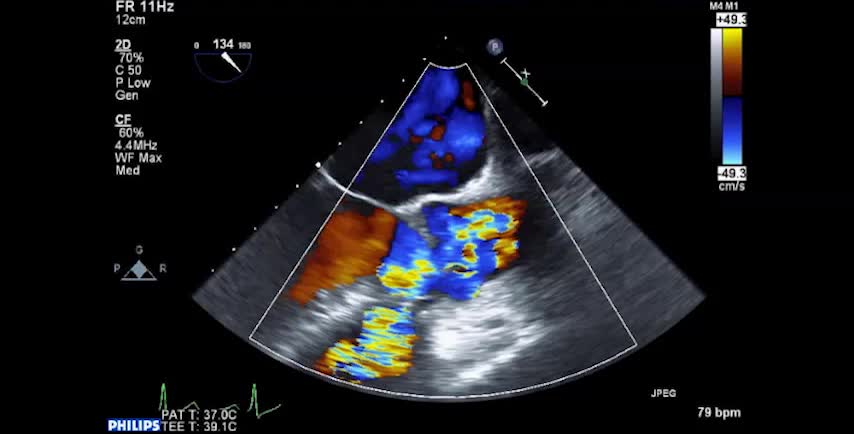

• 症例5 70代女性.僧帽弁狭窄症

• 図4 心エコー図、手術所見 a